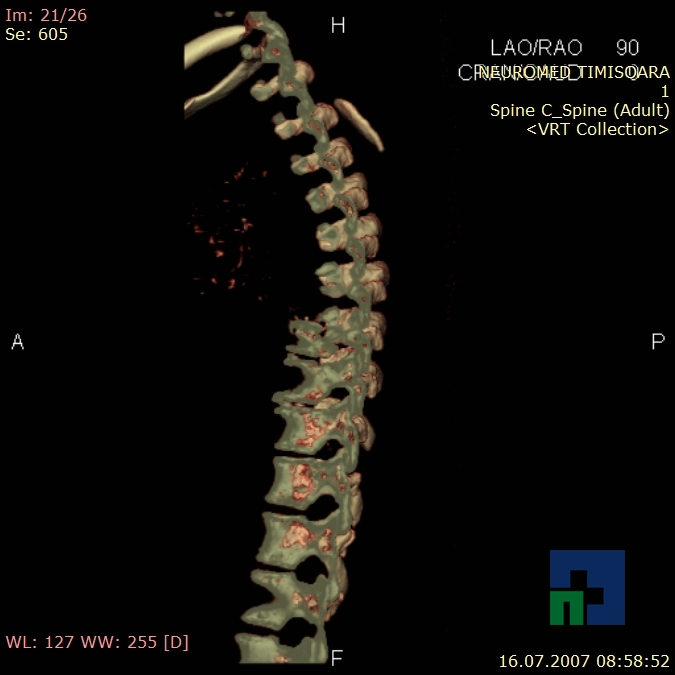

Examinare de rutină cerebrală, nativ și cu substanță de contrast (SDC) pentru diagnosticul:

- Accidentelor vasculare cerebrale ischemice sau hemoragice

- Tumorilor cerebrale